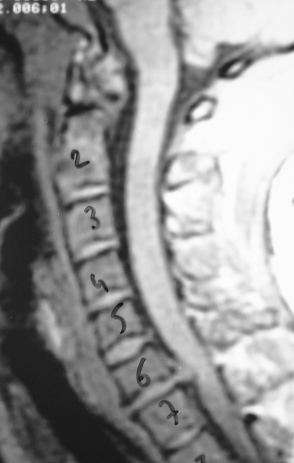

Güncel Servikal MRG - Os Odontoideum ve C1 Kayması

Resim 2: T2 ağırlıklı servikal MRG'de dens'in C2 gövdesinden ayrışarak kranial ve hafifçe posterior yönde deplase olduğu, C1 (atlas) ön arkusunun ise hafifçe geriye kayarak densin bulunması gereken lokalizasyona geldiği görülmektedir. C6 ve C7 vertebra gövdeleri füzyonlu, C5-C6 diskinde ise bulging mevcuttur.